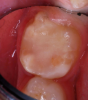

The repaired molar is shown immediately after treatment (Figure 4) and at 13 months (Figure 5). It was hoped that the restoration of the molar would last long enough that stainless steel crown full coverage would not be needed before precision cast crown placement late in the teen or adult years. However, stainless steel crown coverage could be considered, as needed, pending more eruption of the tooth.

Images of the repaired molar immediately after restoration

Figure 4

13 months postoperatively

Figure 5